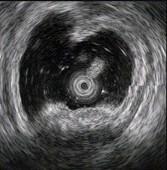

问题 患者,男,59岁,上腹不适2周,查体:心肺腹未见异常。电子胃镜图片及超声内镜如下,进一步要做的最佳治疗方案为 ( )

选项 A.电子胃镜下切除 B.外科手术切除 C.电子胃镜联合腹腔镜切除 D.随访观察 E.口服抗肿瘤药

答案 C